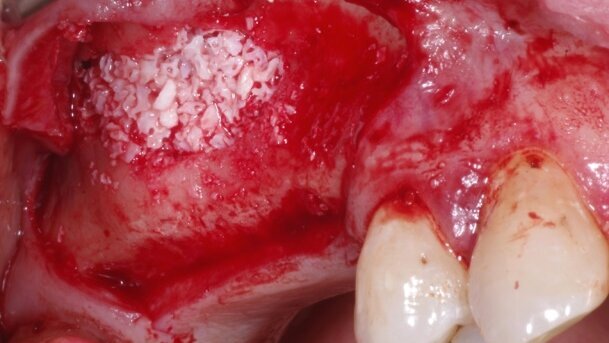

Na rycinach 1-6 przedstawiono fragmenty zabiegów podniesienia dna zatoki szczękowej, gdzie dokonano zamknięcia ran nicią dPTFE.

Materiałem szewnym użytym w tych przypadkach był Coreflon – materiał szewny wykonany z włókna dPTFE, które zostało zespolone z wysokiej jakości igłą wyprodukowaną z unikalnego stopu metali. Coreflon jest owocem długoletnich badań eksperckiej grupy infini-Ti.com. Z uwagi na wysokiej jakości igłę oraz optymalną długość nici wynoszącą 55 cm, we wszystkich przedstawionych i podobnych przypadkach klinicznych do zespolenia tkanek średnio zużywa się 1 opakowanie nici (niezależnie od techniki szycia, przy wiązaniu z wykorzystaniem narzędzia).

Analiza przydatności klinicznej nici o długości ok. 45 cm. wykazała, źe większość bardziej skomplikowanych procedur chirurgicznych wymagała użycia 2 opakowań materiału szewnego. Nici dłuższe (ok. 75 cm) są mało wygodne w stosowaniu: utrudnione jest wiązanie z użyciem instrumentu, a także częściej występuje możliwość ich zainfekowania w ograniczonym polu zabiegowym. Coreflon występuje w grubościach od 3-0 do 6-0 i jest wyposażony w różne igły o nowoczesnej geometrii. Doskonałe dopasowanie średnicy igły do średnicy włókna teflonowego skutkuje znaczną redukcją krwawienia po zabiegu. Nici PTFE są produktem droższym w porównaniu z innymi materiałami szewnymi. Biorąc pod uwagę ich unikalne właściwości, a tym samym możliwość redukcji powikłań dotyczących kosztownych zabiegów, fakt ten wydaje się w tych przypadkach mało istotny.